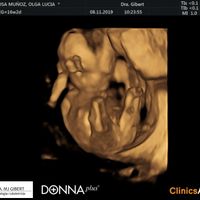

Bienvenidas al grupo futuras Mamis de abril 2020... He creado este grupo nuevo ya que solo se pueden modificar desde el PC y Patricia no puede estar tan pendiente. Soy Cris, este será nuestro primer...